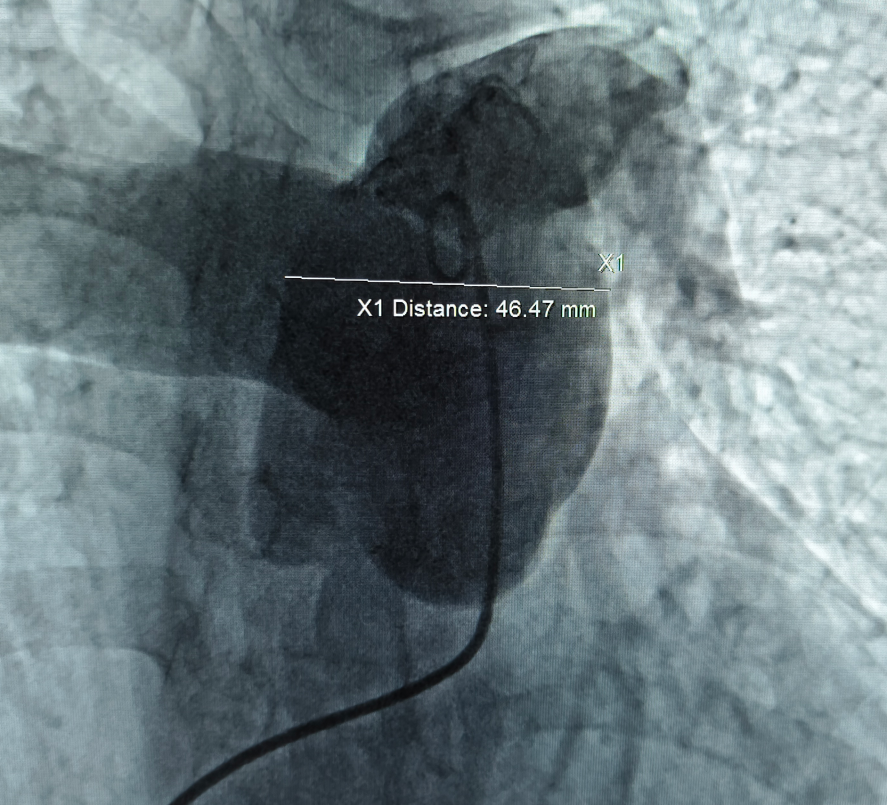

经皮肺动脉去神经术属于微创介入治疗。术前常规行右心导管检查后,交换猪尾巴导管进行肺动脉造影。

肺动脉造影

通过对比术前超声、CT报告及术中造影,选定消融靶点和50mm射频消融导管(按测量直径1.1-1.2倍选择导管)。交换导丝导管,建立消融通道。